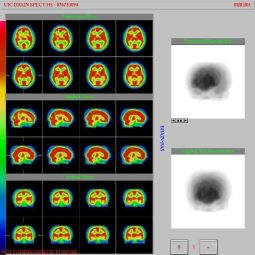

Muerte cerebral vista plana